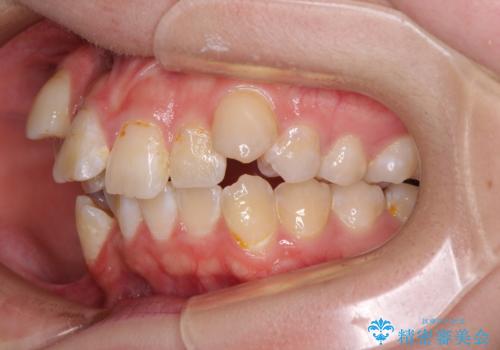

転位歯や埋伏歯などの難易度の高い抜歯矯正治療

- 八重歯や埋伏している奥歯など、多くの難しい問題を抱えている患者様です。

重度叢生のため、大臼歯をしっかりと咬合させるために、下顎は左右第二小臼歯を、上顎は前歯部の叢生を解消するために左右第一小臼歯を抜歯し、口元の突出感を改善するために、上顎大臼歯が前方に移動しないようにするために、補助装置による架強固定を行うこととしました。

叢生は思ったよりも早期に改善されましたが、舌の突出癖による上下前歯の非接触が全く改善されず、2年間ほど治療期間が延びる結果となってしまいました。